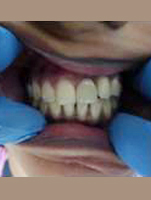

Use of Bone Graft & GTR membrane for an Implant

After Placement of Prosthesis